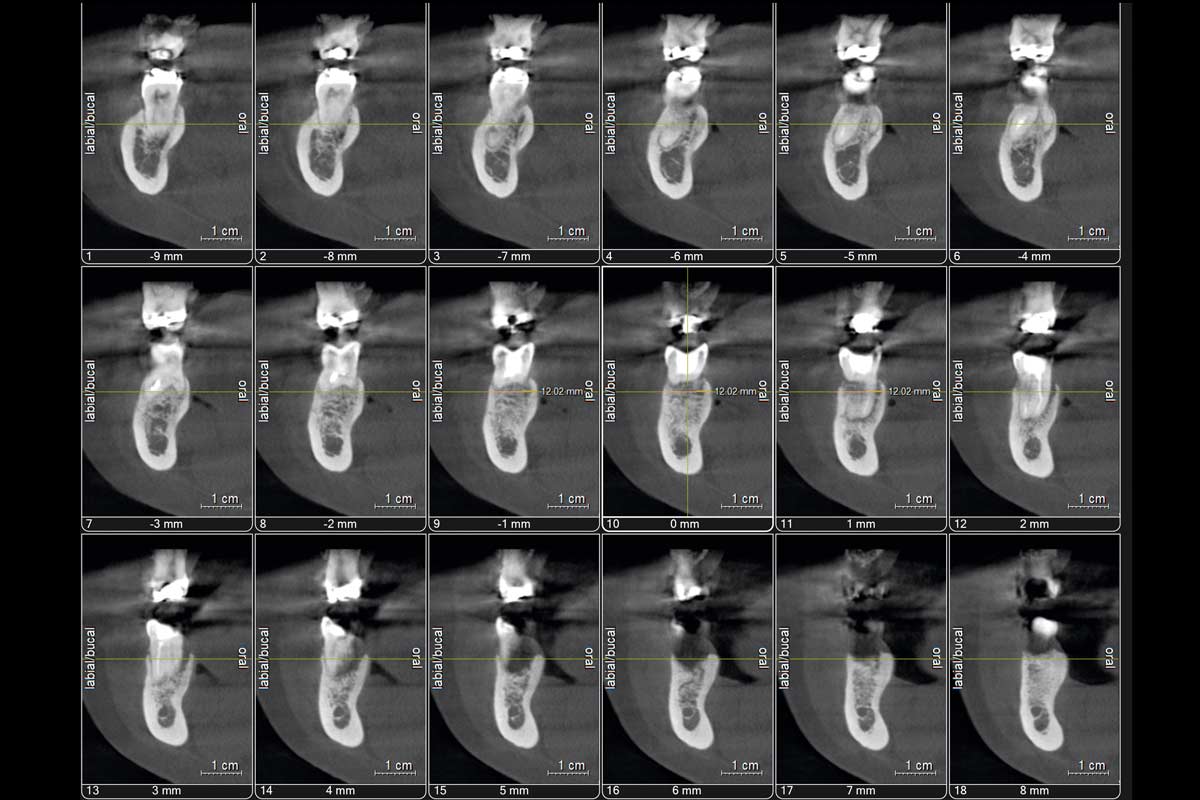

The patient presented with a terminal fracture of the crown tooth number 12